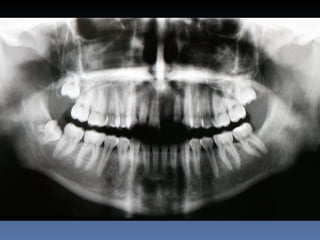

Silvana Ferraz Caetano

Idade – 53 anos

Sexo – Feminino

Raça – Caucasiana

ASA – II

Data- 26-04-2012

Diagnóstico:Desdentada parcial-maxila

Plano de tratamento:          Reabilitação das áreas

desdentadas com instalação de 6 implantes endo-

ósseos para reabilitação protética fixa.